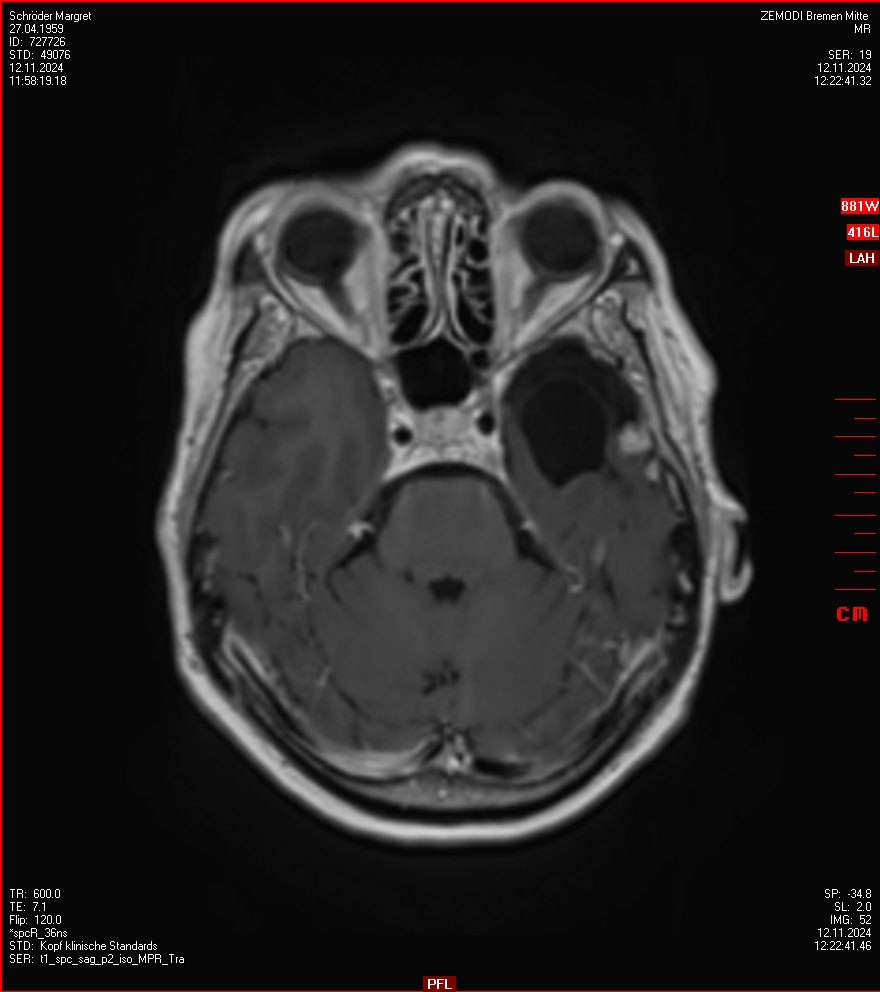

MRT vom 12. November 2024

So nun ein paar neue Bilder aus meinem Kopf. (Durch klicken bekommt man eine größe Ansicht eines Einzelbildes).

Die letzten drei Bilder Zeigen aus meiner Sicht den Tumor, der im Jahr 2021 bestrahlt wurde.

Ich denke, in den letzen 12 Monaten sind da ein paar Rezidive gewachsen,  vor 12 Monaten waren sie auch schon zu erkennen - vorher noch nicht. Nun hoffe ich auf den Rat des Spezialisten. Hoffendlich kann man etwas machen.